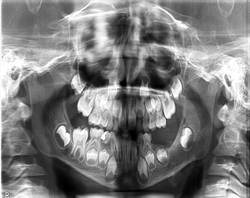

Este paciente ha estado en seguimiento en consulta externa de Cirugía Maxilofacial durante un año, realizándose los chequeos radiográficos periódicos pertinentes, a los 3, 6 y 12 meses respectivamente como se puede ver en las (Figuras 5, Figura 6 y Figura7).